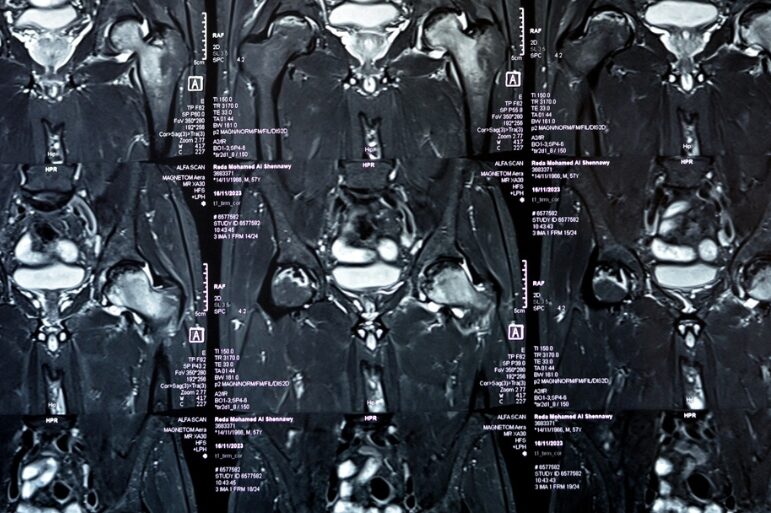

Στη συνέχεια η σημαντικότερη απεικονιστική εξέταση για την επιβεβαίωση της διάγνωσης είναι η μαγνητική τομογραφία (MRI). Η συγκεκριμένη εξέταση μπορεί με ευκολία να ανιχνεύσει αλλαγές στον μυελό των οστών και να εντοπίσει την παρουσία υγρού ακόμη και σε πρώιμα στάδια της πάθησης.